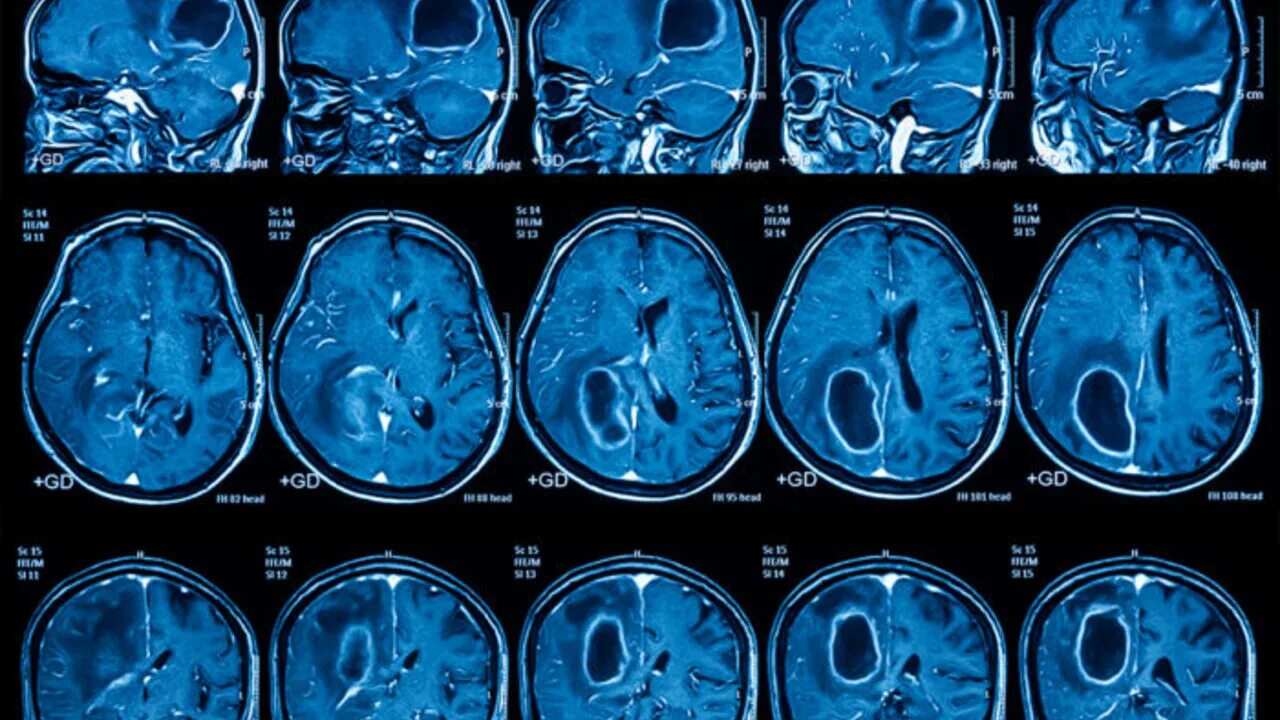

После мрт головного мозга